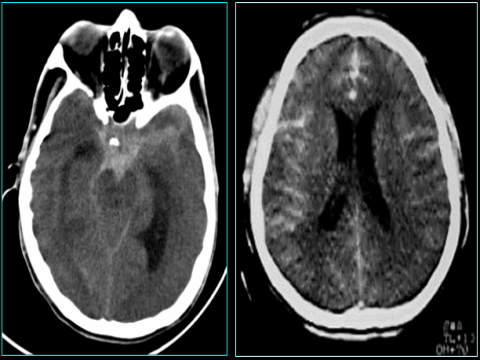

Kết quả bước đầu can thiệp nội mạch điều trị phình mạch não vỡ tại Bệnh viện Trường Đại học Y Dược Cần Thơ